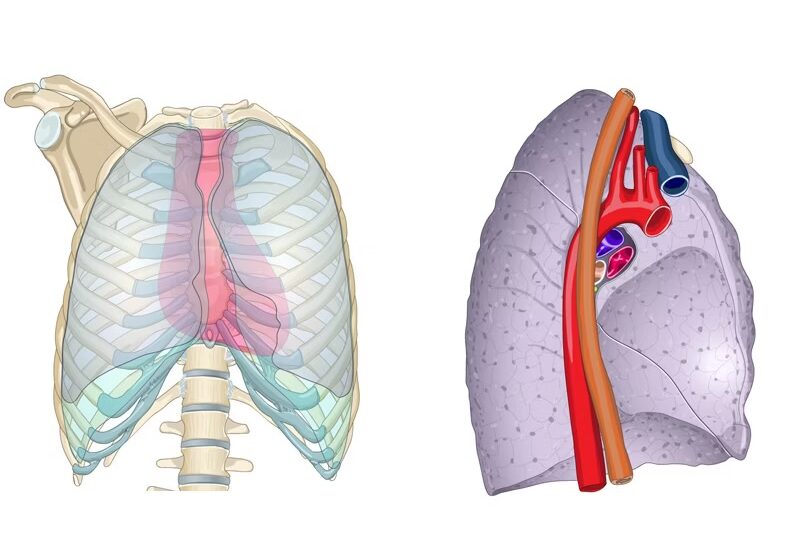

La forma general de cada pulmón se asemeja a la de un semicono, con un vértice superior y una base inferior. Esta forma es adaptativa y permite que los pulmones se ajusten adecuadamente dentro del tórax, maximizando la eficiencia del intercambio gaseoso durante la respiración. Al describir la forma de los pulmones, se pueden identificar varias características:

- Tres caras:

- Costal: esta es la cara que está en contacto con las costillas y la cavidad torácica.

- Mediastínica: esta cara está orientada hacia el mediastino, la región central del tórax que contiene el corazón, los grandes vasos sanguíneos y otros órganos.

- Diafragmática: esta es la cara que se encuentra en contacto con el diafragma, el músculo principal involucrado en la respiración.

- Un vértice: este es el punto superior del pulmón, que generalmente se encuentra cerca de la clavícula.

- Dos bordes:

- Anterior: este borde se encuentra en la parte delantera del pulmón y puede ser más agudo o redondeado, dependiendo de la forma individual del pulmón y la anatomía circundante.

- Inferior: este borde se encuentra en la parte inferior del pulmón y se extiende a lo largo del diafragma.

- Una base o circunferencia inferior: esta es la parte inferior del pulmón que descansa sobre el diafragma y forma una superficie cóncava.